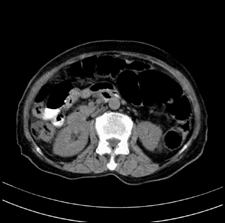

患者,女,75岁。腹痛,体黄5日,膝胸位时腹痛缓解。肝功能明日出来。彩超提示胆总管占位,未见血流信号。心电图提示s-t段改变。患者体质较弱,未能增强。

胆总管多发结石伴肝内外胆管轻度扩张。

胆总管上段,腔内有软组织密度影 ,ct值36-44hu。大家看有没有胆管癌的可能。

2楼所说胰腺内钙化不像,象脾脏血管的钙化

典型胆总管多发结石;增强扫描前后ct值是否发生改变是鉴别结石与占位的依据。

典型的胆总管多发结石。在没有增强的情况下,暂不考虑其他。

胆管没有鼠尾征,还是考虑结石